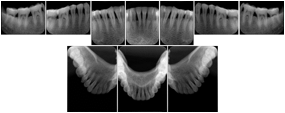

In most standard cases, images are oriented in structured layouts. These structured displays are useful to be shared between providers for reference purposes.

Table OO.1.1-1 shows structured display standard templates, where Viewset ID is based on the Japanese Society for Oral and Maxillofacial Radiology (JSOMR) classification provided by JIRA (Japan Medical Imaging and Radiological Systems Industries Association, www.jira-net.or.jp). Expected or typical teeth to be imaged location, region and designation codes are based on ISO 3950-2010, Dentistry - Designation system for teeth and areas of the oral cavity. For all the hanging protocols listed in OO.1.1-1, the value to use for Hanging Protocol Creator (0072,0008) is "JSOMR" and the value to use for Hanging Protocol Name (0072,0002) does not include "JSOMR" (e.g., "DL-S001A", not "JSOMR DL-S001A").